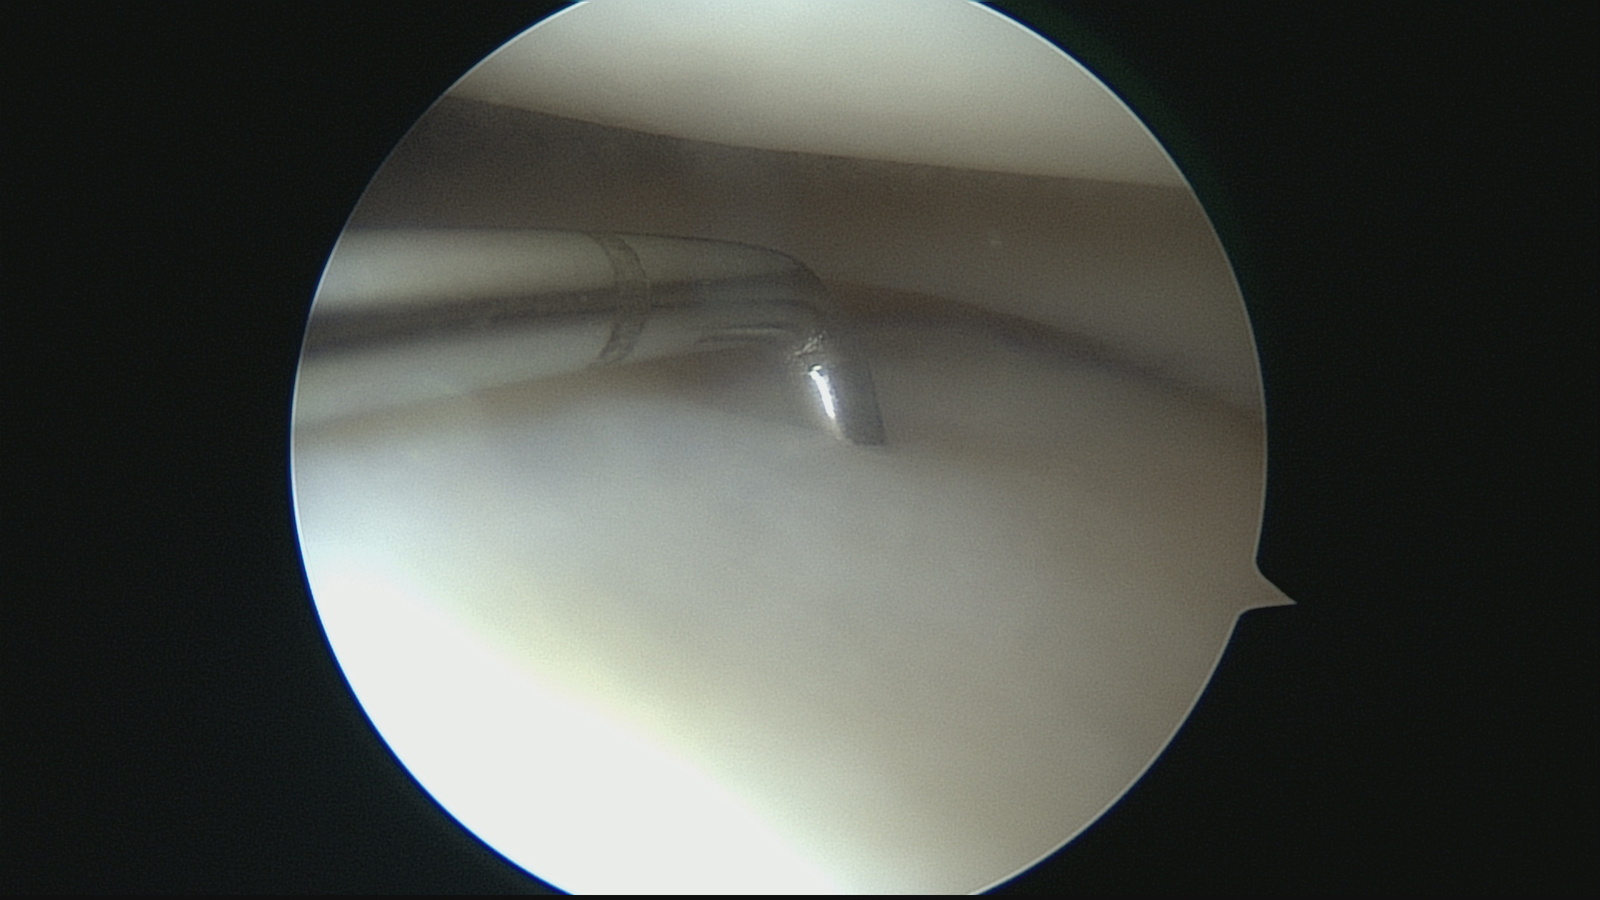

Инструмент - артроскопический крючок ( что то вроде щупа ) этот отдел сустава тоже норм.